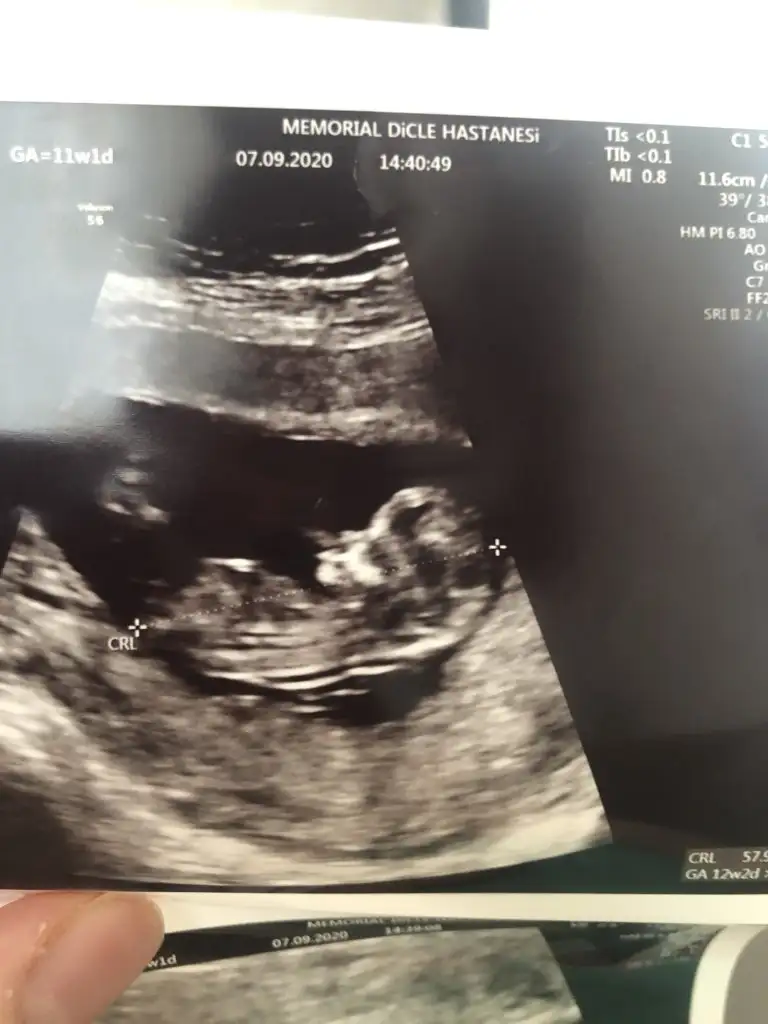

12+5 tahmin edebilir misiniz ? Karından ultrason Ikra meyra Ikra meyra

Ikra meyra Ikra meyra merhaba canım 14. Hafta ultrasonundan tahmin rica etsem 😊